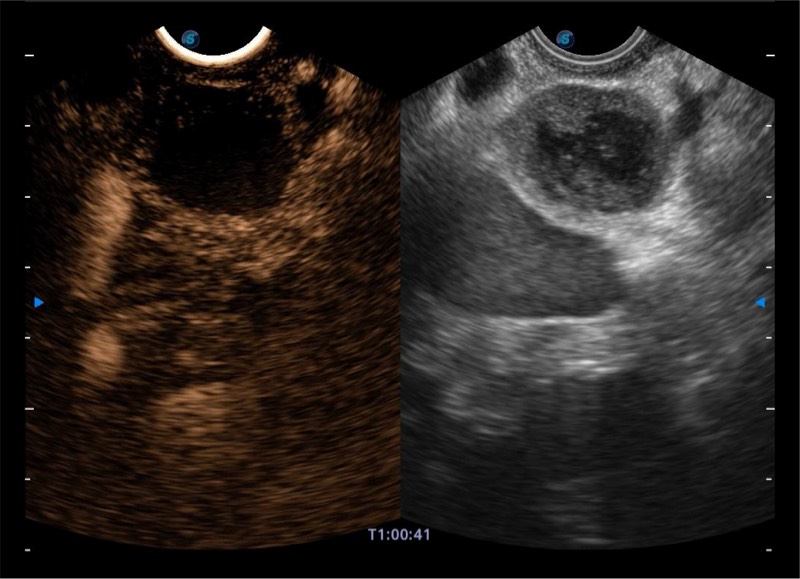

搭载百万级CMOS成像技术

及自主研发凸阵换能器,

可呈现优质的内镜和超声画面

基于二十年的超声技术积累,银河集团官网提供了最新一代的独立超声主机,在提供高质量图像的同时满足多学科使用。具备常见多普勒技术并提供弹性成像、声学造影等高端影像技术。新一代传感器具有更强的抗干扰能力并减少图像伪影。